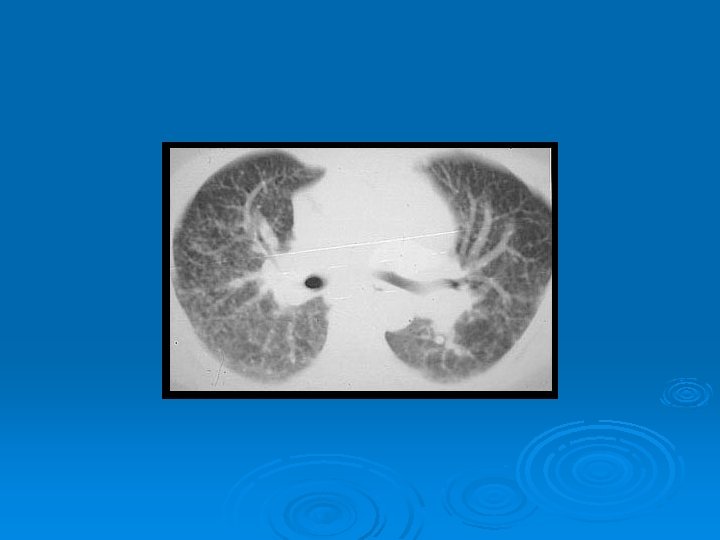

DEĞİŞİK RADYOLOJİK GÖRÜNÜMLER RETİKÜLONODÜLER PATERN

ASİNER PATERN

PNÖMONİK GÖRÜNÜM

ALVEOLER SARKOİDOZ

KAVİTER SARKOİDOZ

HRCT Ø Akciğer grafisine göre daha duyarlı Ø Paratrakeal, pretrakeal, paraaortik ve subkarinal adenopatilerde tespit edilebilir